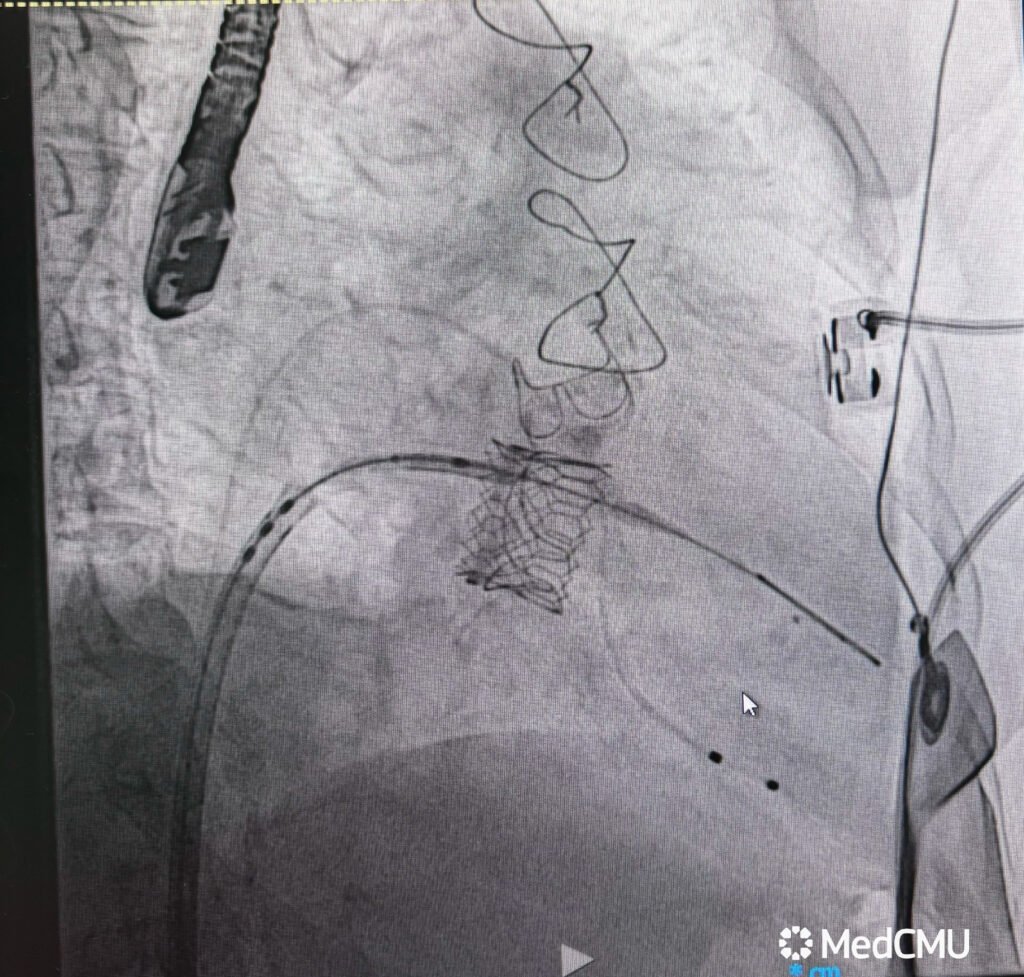

คณะแพทยศาสตร์ มหาวิทยาลัยเชียงใหม่ ประสบความสำเร็จในการรักษาผู้ป่วยหญิงไทย วัย 83 ปี ด้วยเทคนิคการเปลี่ยนลิ้นหัวใจไมตรัลเทียมตัวใหม่ แทนที่ตัวเก่าที่เสื่อมสภาพ ผ่านทางสายสวน โดยเทคนิคการตัดลิ้นหัวใจอันเดิม (LAMPOON – Laceration of the Anterior Mitral Leaflet to Prevent Outflow Obstruction) ถือเป็นรายแรกในระดับภูมิภาคของประเทศไทย ที่มีการทำหัตถการดังกล่าว และเป็นความก้าวหน้าสำคัญในการดูแลผู้ป่วยโรคหัวใจซับซ้อน

อ.พญ.ทรรศลักษณ์ ทองหงษ์ เปิดเผยว่า “เทคนิค LAMPOON ถือเป็นก้าวใหม่ของหัตถการในการรักษาภาวะแทรกซ้อนของการใส่ลิ้นหัวใจเทียม เนื่องจากต้องอาศัยความแม่นยำสูงในการเลาะพังผืดและกรีดลิ้นหัวใจเดิม เพื่อป้องกันการอุดกั้นทางออกของหัวใจ การทำหัตถการนี้ต่างจากการเปลี่ยนลิ้นหัวใจด้วยสายสวนแบบทั่วไป เพราะผู้ป่วยมีลิ้นหัวใจเทียมชนิดเก่าอยู่แล้วซึ่งเสื่อมสภาพจนทำให้เกิดภาวะแทรกซ้อน ซึ่งหากเป็นวิธีการเดิม ผู้ป่วยจำเป็นต้องรับการผ่าตัดเปิดทรวงอกซ้ำซึ่งมีความเสี่ยงสูงมาก แต่ในครั้งนี้ ทีมแพทย์สามารถทำได้สำเร็จ และผู้ป่วยฟื้นตัวได้โดยไม่ต้องเปิดทรวงอก ถือเป็นก้าวสำคัญในการดูแลผู้ป่วยหัวใจที่ซับซ้อน”

ความสำเร็จครั้งนี้สะท้อนถึงความพร้อมและศักยภาพของคณะแพทยศาสตร์ มหาวิทยาลัยเชียงใหม่ ในการนำเทคโนโลยีและนวัตกรรมการรักษาโรคหัวใจขั้นสูงมาใช้ เพื่อยกระดับคุณภาพชีวิตและเพิ่มโอกาสรอดชีวิตให้กับผู้ป่วยในประเทศไทย